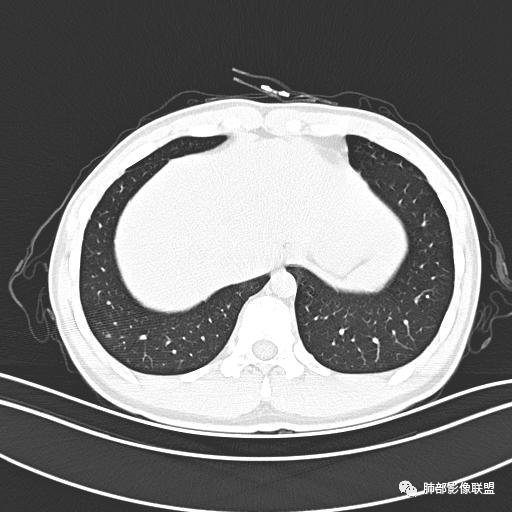

男,19岁

主  诉:发热、全身皮疹2天。

现病史:患者源于2天前受凉后出现发热,最高体温为38.5℃,且颜面部出现少量皮疹,无鼻塞、流涕、咳嗽、咳痰,未在意而未作特殊处理,次日全身皮疹逐渐增多至全身,伴轻度瘙痒,在当地卫生所给予抗病毒、抗感染治疗(具体用药不详)体温有所下降,但皮疹无明显消退,无腹痛、头痛,食欲无明显减退,为进一步诊治,遂于今日急来我院求治,患者目前精神尚可,体力正常,食欲正常,睡眠正常,体重无明显变化,大便正常,排尿正常。

小强:青年,发热,皮疹;双肺散在结节,周围磨玻璃,点晕征,疱疹病毒感染,鉴别荚膜组织胞浆菌,结核。 大雄:青年,急性起病,发热伴全身皮疹2天,抗病毒治疗体温有下降。双肺随机分布大小不等类圆结节,“点晕征”。考虑水痘-疱疹病毒(VZV)血播询问接触史,查体皮疹分布以及形态基本可诊断。 王开金江津中心医院呼吸科:青年男性,起病急,病程短,以发热,皮疹为首发症状,感染指标以单核细胞升高为主,胸部ct双肺多发结界,周围有晕,点晕表现,随机分布,同意於老师意见,水痘疱疹病毒血流感染累及肺。 王秀仙:双肺多发大小不等结节,周围有晕,边缘模糊,呈点晕征表现。青年,急性起病,发热伴全身皮疹2天,抗病毒治疗体温有下降。考虑疱疹病毒。鉴别荚膜组织胞浆菌。 傅昌瑜:19岁男性,发热、全身皮疹2天,单核细胞增高,双肺多发结节,结节边缘见边界不清磨玻璃影。点晕征+发热、全身皮疹+单核细胞增高——考虑水痘-带状疱疹病毒肺炎。 一切∮随缘:年轻男性,发热,皮疹两天,实验室,CRP,PCT增高,影像:双肺多发散在磨玻璃结节,边界欠清,大小不等,呈点晕征改变,以血管束周围分布为主,局部血管束略增粗,其它无明显改变,考虑:1:病毒性肺炎(水痘疱疹病毒?不知道皮肤有无改变)2:真菌(组织胞浆菌,血管侵袭性肺曲霉)3:GPA4:寄生虫(实验室没有看到嗜酸细胞增高) 赵山河:双肺散在结节,周围有晕,边缘模糊,呈点晕征表现。青年,急性起病,发热伴全身皮疹2天,抗病毒治疗体温有下降。考虑水痘—疱疹病毒感染。洪桥爱:青年男性,发热、皮疹2天,伴瘙痒,皮疹于面部首发,之后进展至全身,虽然没有对皮疹进行描述,但是从出疹时间及皮疹进展情况,伴瘙痒,应该就是个水痘患者;CT提示双肺随机分布结节影,部分结节伴有边界不清晕征,考虑水痘血播肺。 刘强:年轻男性,急性起病,皮疹,发热,抗感染治疗体温下降,说明有效。影像表现为散在点晕征,感染类疾病谱(疱疹病毒,真菌,结核),结合年龄,皮肤皮疹,考虑水痘-疱疹病毒性肺炎。 小兜:男性,19岁,发热皮疹两天,颜面部至全身,CRP,降钙素及单核增高。CT示双肺散在小结节,周围伴磨玻璃影,点晕征,考虑为水痘-带状疱疹病毒(varicella-zoster virus,VZV)肺炎 必有路:青年,皮疹+发热+“点晕征”→水痘-疱疹病毒(VZV) 许慧良:青年男性患者,发热、皮疹2天,体温最高38.5℃,第3天皮疹扩展至全身,伴瘙痒,胸部CT:双肺多发随机分布的小结节,结节周边见边界模糊的晕征,考虑水痘病毒感染流心明智:男,19,急性起病,发热伴全身皮疹2天。出疹顺序头→全身,抗病毒有效。胸部CT:两肺多发大小不等类圆形实性小结节影,随机分布,结节周围环绕GGO,边界模糊,呈点晕征。出疹特点是关键,未提示。考虑:血播病毒性肺炎,水痘-疱疹病毒?麻疹?鉴别荚膜组织胞浆菌、TB、血管炎、寄生虫等。 浪迹天涯:病灶多为5-10mm大小结节,结节周围可见磨玻璃样的晕环,常多发,可分布于肺内任何区域,考虑水痘—带状疱疹病肺炎如果短时间内有新的一个区域浸润,更加能说明,